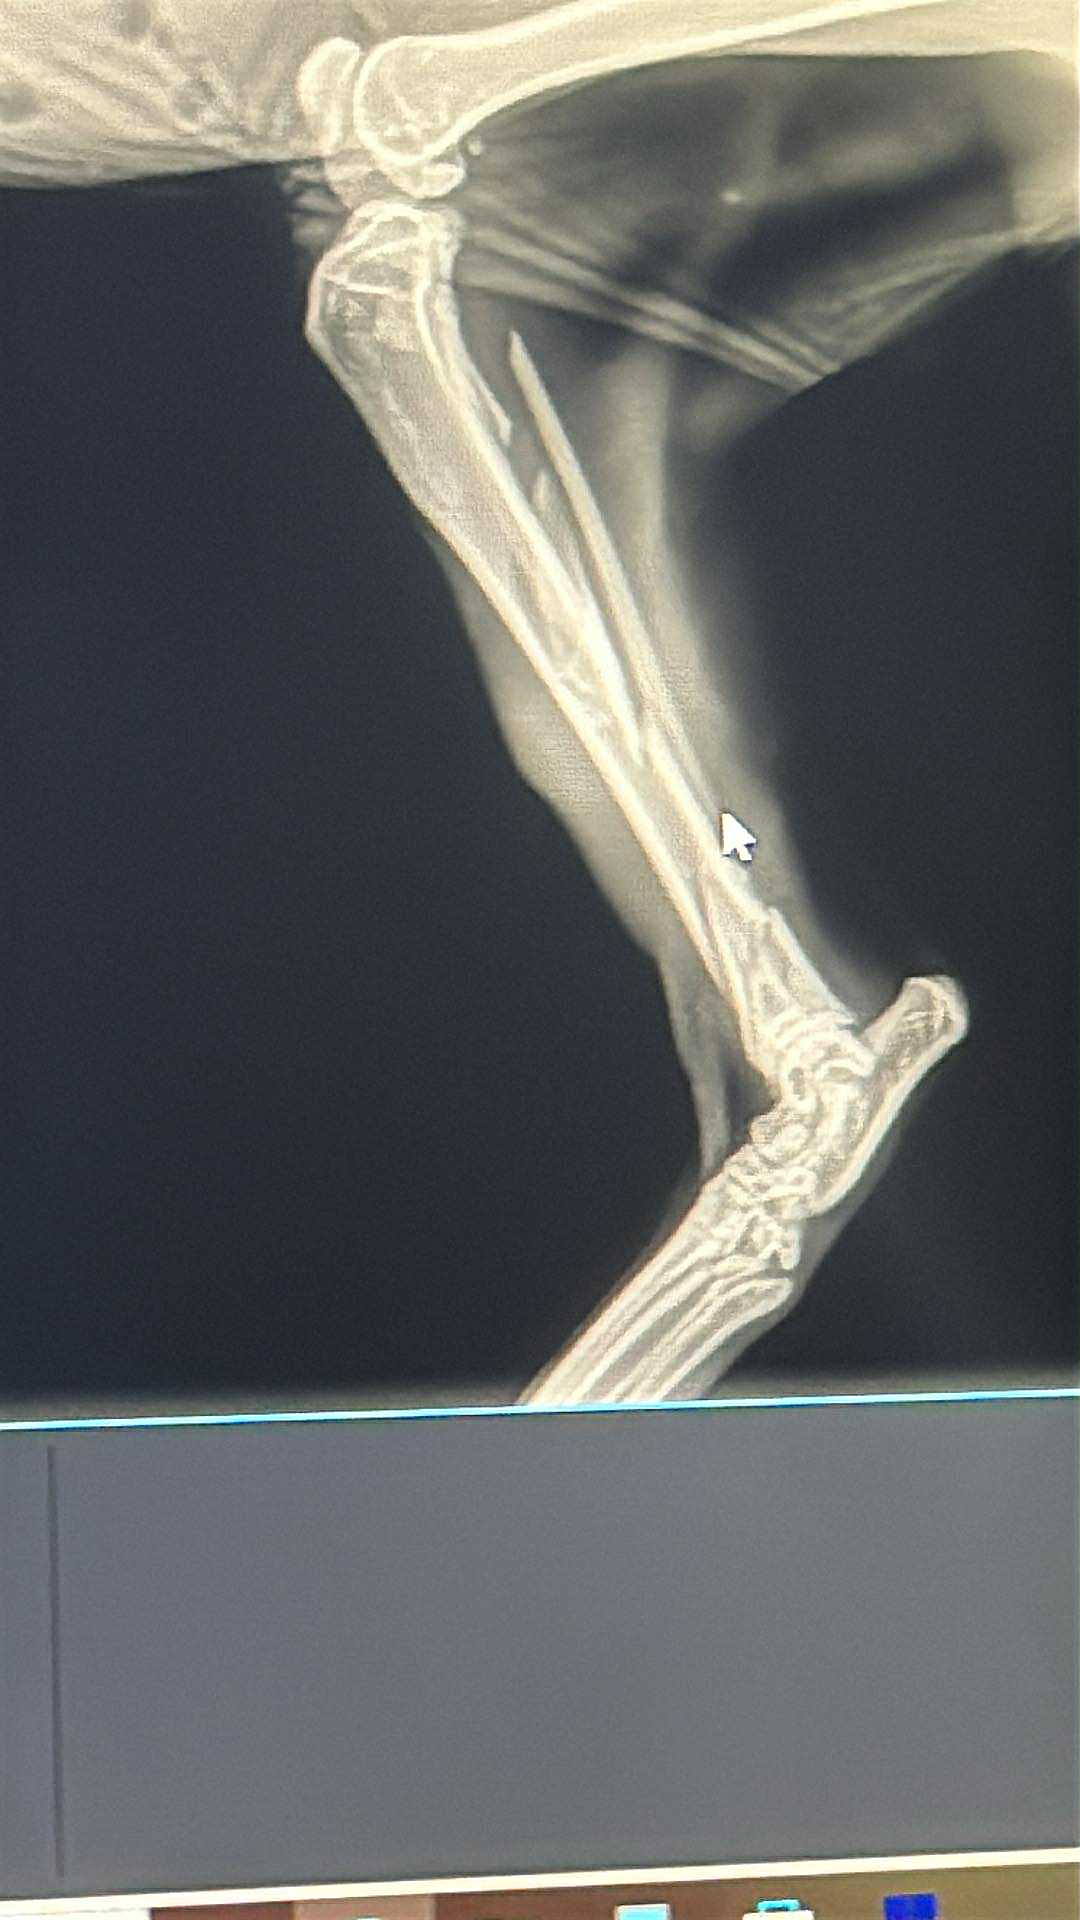

Mr. Bigglesworth was found in a parking lot eight days ago very skinny with a broken leg.

mr. Bigglesworth was found in a parking lot eight days ago with a broken leg ear mites, and an upper respiratory infection and very skinny. We picked him up and brought him home trying to find an owner. The owner was found so we started seeking care to help him recover to give him the best life possible we found out he is about seven years old the Vet had said it looks like Mr. Bigglesworth had either been hit by a car or someone had kicked him with such tremendous force that his leg had been broken and three different pieces because of his age and because of how long he was out on the leg before he was found it’s not known if the leg is going to be able to be saved so at this time, we are starting a donation to prepare for the surgery to fix his leg and give him a new life he’s the sweetest cat and absolutely loves attention and just wants to be loved. We want to give him the best chance possible.